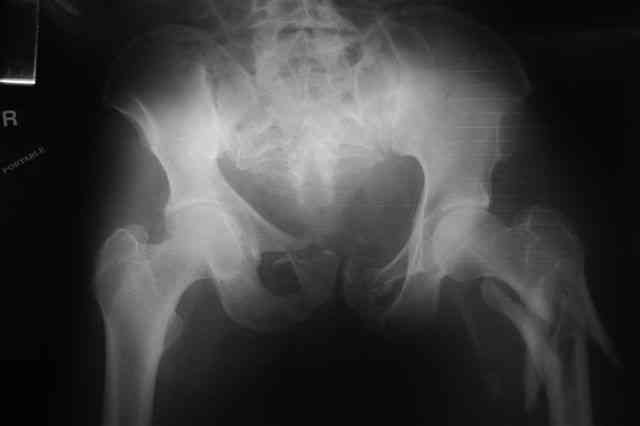

В приложении отправляю послеопер. снимки бедра и лодыжки обсуждаемого вчера больного.

В приложении послеоперационные картинки.

Чекашкин Е.И.